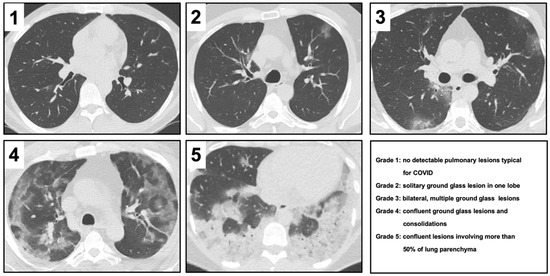

2.3. Severity Score in CT